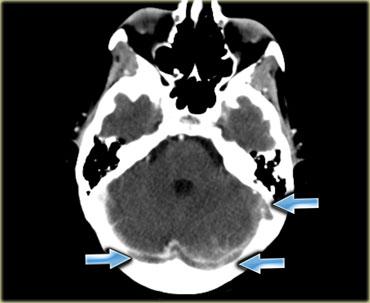

Dấu hiệu delta rỗng (2)

Hình ảnh bên trái là một trường hợp huyết khối xoang ngang phải và xoang ngang-xoang sigma trái (mũi tên).

Có hình ảnh ngấm thuốc bao quanh các tĩnh mạch giảm tỷ trọng bị huyết khối.